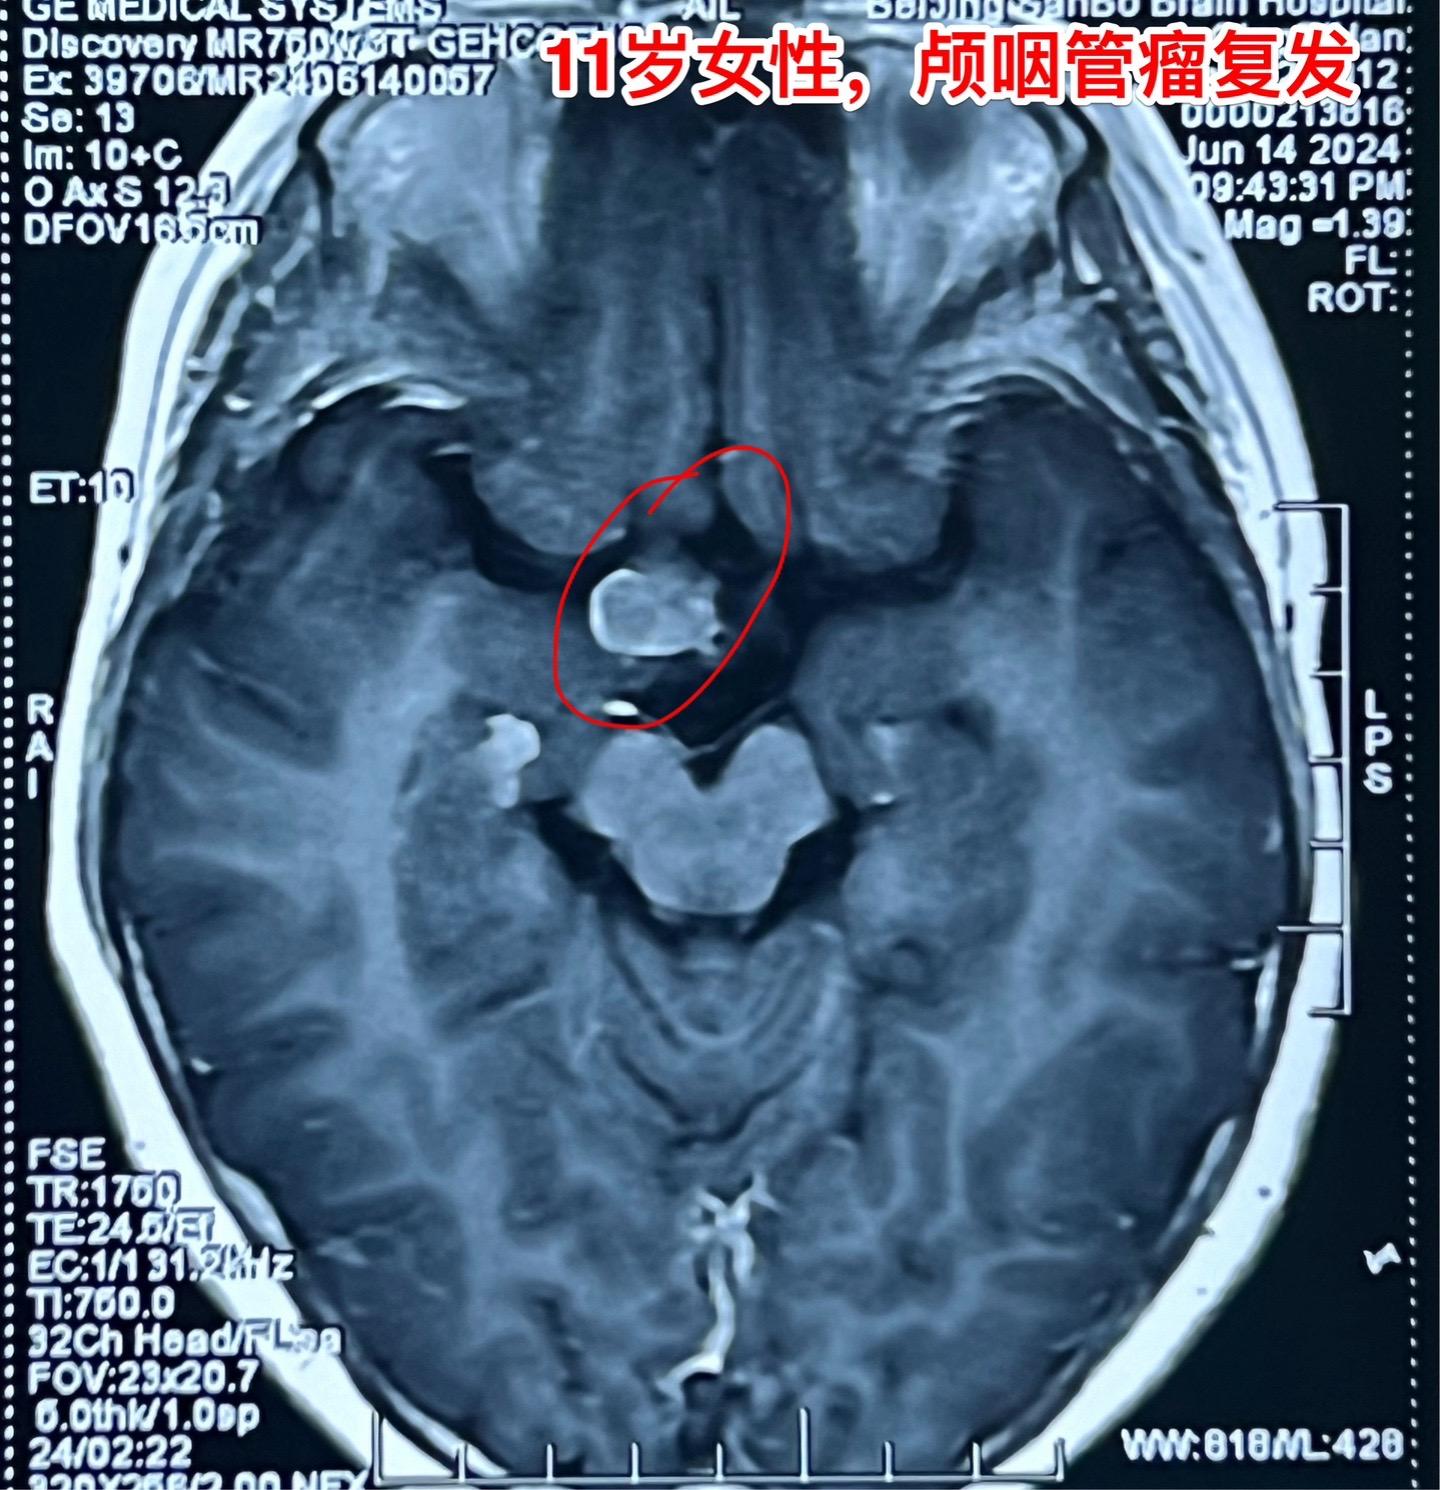

颅咽管瘤复发,病人该如何面对?11岁四川女孩子,颅咽管瘤复发了! 距离第一次经鼻内镜手术不到一年时间,颅咽管瘤就复发了,右眼视力下降。所以只能再次手术 近3年时间内我们科遇到的经鼻手术后复发的颅咽管瘤病例数呈显著增长趋势。在2024年完成的90例颅咽管瘤中,经鼻手术后复发者占比为12.2%。 这个增长趋势与近年来中国开展经鼻内镜手术切除颅咽管瘤例数的增长趋势是一致的。 4月21日我们作了开颅手术,将肿瘤完全切除了。 颅咽管瘤是神经外